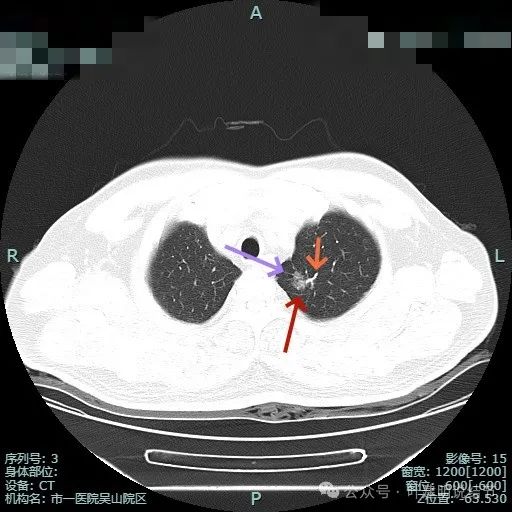

边缘毛刺,血管进入,灶边有细支气管扩张,整体轮廓与边界清。

血管异常增粗进入,灶内小空泡征,表面不平有浅分叶,灶内密度感觉欠均匀。

血管进入,边缘细毛刺,灶内小空泡,少许实性成分,表面不平毛糙。